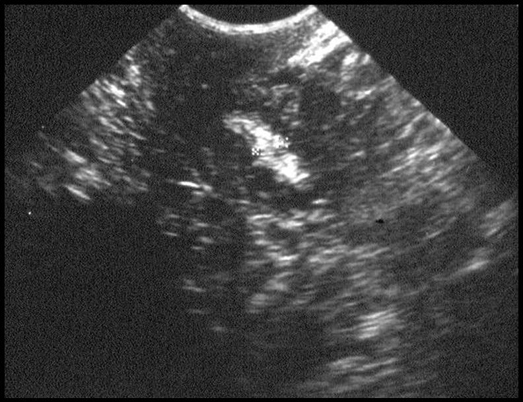

Caillots. Hyperéchogène, aspect de polype, image mobile. Pas de flux au Doppler couleur